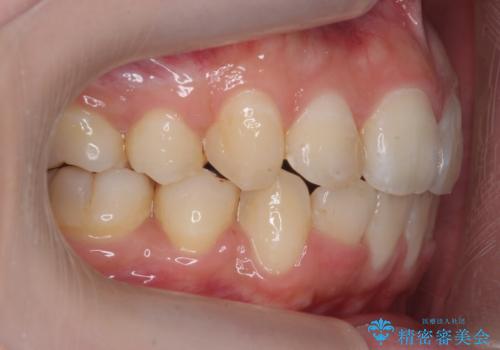

治療に時間はかかりましたが、喜んでいただけました。

矯正後は口も閉じやすくなり、大変喜んでいただけました。

2-3年かかりますが、その後の70年の方が、長いのではないかと思います。